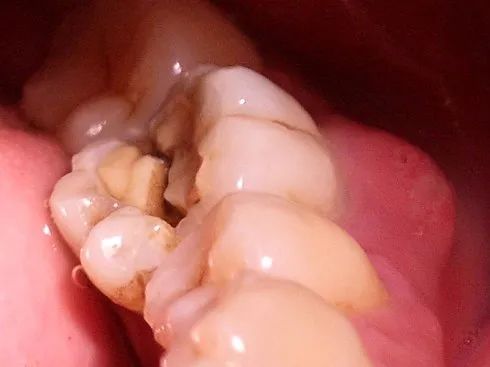

不可修复性牙折的诊断与治疗一例_检查_裂纹_远中